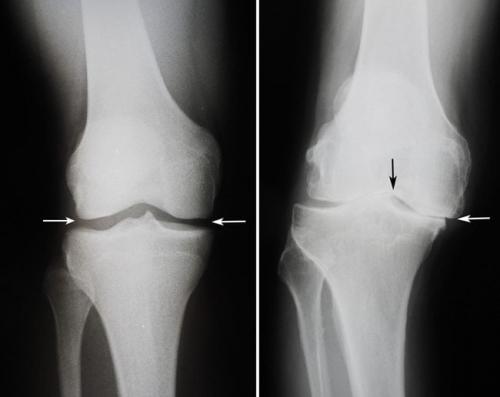

- Комплексные суставы (articulatio complex) — имеют суставной диск или мениски (грудино-ключичный, височно-нижнечелюстной, коленный).

Коленный сустав. Какие бывают болезни коленного сустава: список самых распространенных

частые патологии опорно-двигательного аппарата. Около 15% пациентов ортопедо-травматологических стационаров попадают туда именно из-за проблем с коленями. Давайте посмотрим, какие бывают болезни коленного сустава.

При отсутствии лечения некоторые травмы и заболевания колена могут приводить к снижению трудоспособности и даже инвалидности. Если вас беспокоят боли,или другие неприятные симптомы – немедленно идите к врачу! Своевременная медицинская помощь поможет вам избежать тяжелых последствий.

В зависимости от причин возникновения все болезни коленных суставов можно разделить на несколько больших групп. Для каждой из них характерны свой механизм развития и симптоматика.

Виды заболеваний коленных суставов:

- воспалительные. Характеризуются развитием инфекционного или асептического воспаления различных структур коленного сустава. Могут возникать в любом возрасте. Причины патологиизанесение инфекции в сустав или наличие воспалительного процесса в организме.может быть как острым, так и хроническим. Воспалительные процессы также могут развиваться на фоне длительного течения;

- дегенеративно-дистрофические. Чаще встречаются у пожилых людей и лиц, которые постоянно выполняют тяжелую физическую работу. Дегенеративные процессыэто следствие старения организма, которое сопровождается замедлением метаболизма и кровообращения в суставах. Под действием провоцирующих факторов (физические нагрузки, нехватка кальция, обменные нарушения) суставные хрящи начинают разрушаться, что приводит к развитию патологии. Дегенеративно-дистрофические заболевания имеют хроническое, медленно прогрессирующее течение;

- травматические . Возникают сразу после травмы или позже, в более отдаленном периоде. Причиной может быть падение,, удар по колену или сдавление ноги тяжелым предметом. Травматические заболевания могут приводить к нарушению функционирования коленных суставов, трудностям при ходьбе и даже инвалидности. Их своевременное лечение помогает избежать нежелательных последствий;

- опухолевые . Новообразования в области колена могут быть доброкачественными и злокачественными. К первым относят остеому и, которые хорошо поддаются лечению. Ко вторым относятся множественная миелома, хондросаркома, остеогенная саркома. Как и любые злокачественных опухоли лечить их сложно. Развиваются они редко.